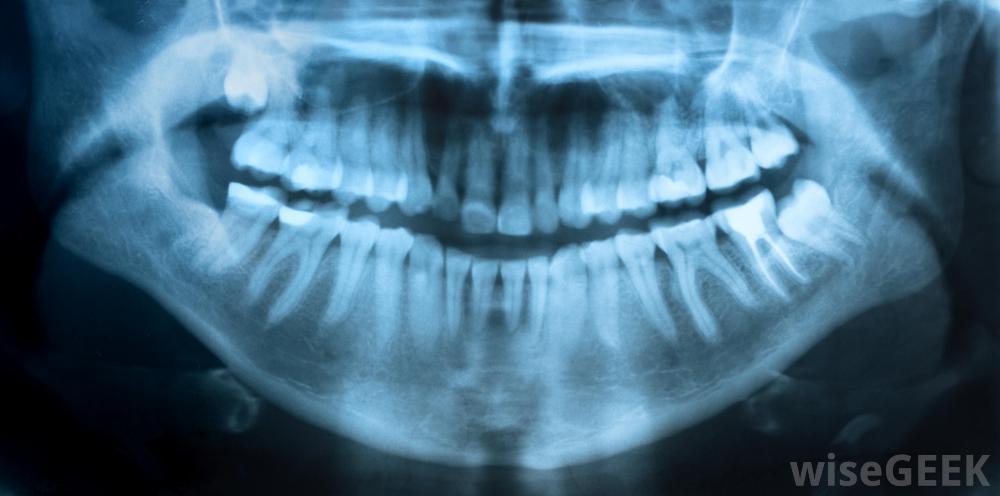

如果你正在经历补牙的疼痛,你需要考虑一下最近你在牙齿里植入了填充物。新的填充物可能需要一段时间的调整,因此,你可以使用非处方药或局部止痛药来缓解你的不适,直到你的口腔痊愈,你习惯了新的牙科工作。另一方面,牙齿填充物疼痛可能是你的填充物之一已经开裂或移动,开始腐烂的迹象。疼痛也可能是填充物放置不当的迹象,所以最好是联系你的牙医,安排一个预约,让他或她检查你的牙齿,找出你疼痛的原因。各种治疗方法从使用非处方止痛药到更换充填物到严重受损牙齿的根管残牙是充填后牙痛的一个原因。当你填满牙洞后,你的牙医可能会告诉你,你的牙齿可能会有一段时间的敏感。虽然这种敏感通常是暂时的,但它会让你感到不舒服,所以在治疗之后,你可以做一些事情来解决牙齿填充物的疼痛问题。首先你要做的是避免食物和行为引起敏感。对很多人来说,非常热或非常冷的食物和饮料,以及一些糖果,都会引发牙齿和牙齿填充物的疼痛。避免这些食物和饮料,以防几周后,你的嘴就会习惯这种填充物。市面上有各种各样的牙膏是为敏感牙齿而配制的,经常使用它们可以大大降低牙齿的敏感性和不适感牙齿感染会导致疼痛。如果您发现您的牙齿在接受补牙后的几周内仍然敏感,或者您在一段时间前补牙后开始感到疼痛,请联系您的牙医。你的牙医可以检查你的牙齿并要求进行x光检查,以帮助他或她了解什么可能导致你的牙痛。如果发现感染,他或她可能会开抗生素,你可以讨论各种治疗牙齿的方法。你的牙医可能会帮你更换填充物,把牙冠放在牙齿上,或者,如果有必要,建议做根管治疗很重要,由于龋齿通常是渐进性的,可能会对牙齿和口腔造成严重损害,甚至可能导致身体其他部位的疾病。如果有人在应用填充物时,应咨询牙医。可能需要x光片来确定牙齿受伤的原因患者在填充后可能会感到牙痛。